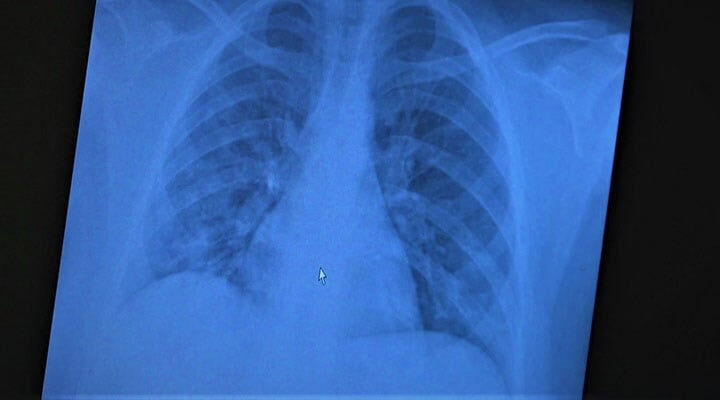

ABD'de yapılan yeni bir araştırmaya göre, Salton Denizi’nden yayılan 'zehirli' tozun artması, bölgede yaşayan çocuklarda ölçülebilir düzeyde akciğer hasarına yol açıyor.

Sonuçlar, denize yakın yaşayan çocuklarda akciğer fonksiyonlarının daha düşük olduğunu ve "1930’lardaki toz fırtınası zatürresi"ne benzer solunum problemleri görüldüğünü ortaya koydu.

Bilim insanları, Salton Denizi tozlarının yüksek miktarda bakteriyel zar parçacıkları içerdiğini ve bunların güçlü endotoksinler olarak akciğer hasarını artırabileceğini belirtiyor.